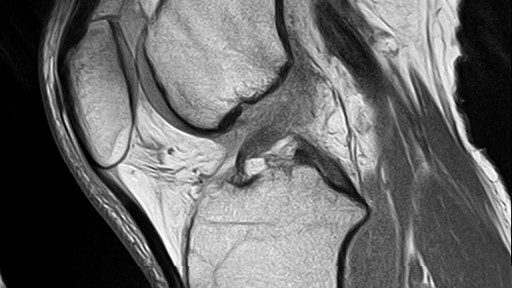

Complete ACL tear

MCL tear

The MRI indicates:

The MRI shows the continuity of the ACL. His doctor diagnosed this case as the spontaneous healing of the ACL tear. There was still some signal intensity on the MCL.